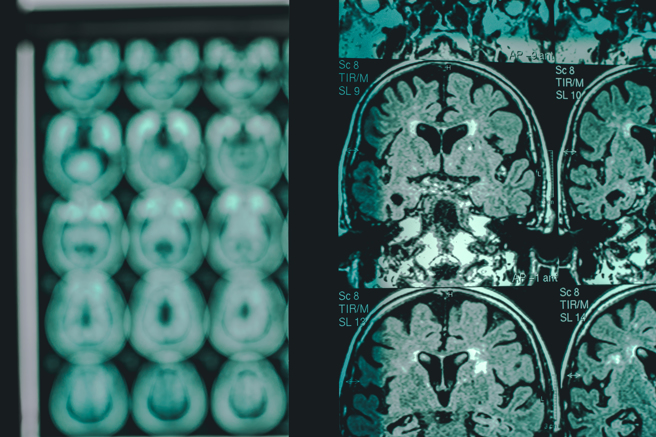

1984年科学家们查明造成大脑神经斑块的主要成分是β淀粉样蛋白,后续研究也钻研于去除β淀粉样蛋白的沉积做为治疗策略,但多年来成效不彰。(图/Shutterstock)